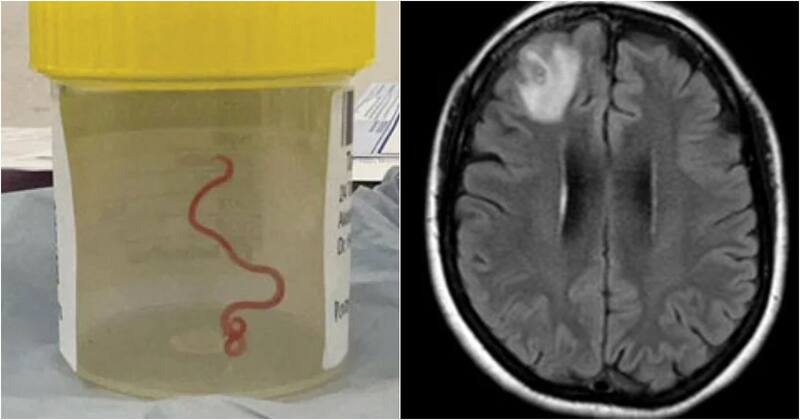

El caso de una mujer australiana de 64 años ha impactado a la comunidad científica y al mundo. Y es que luego de ingresar a un hospital en enero de 2021 tras sufrir tres semanas de dolor abdominal y diarrea, seguidas de tos seca, fiebre y sudores nocturnos, encontraron un gusano parásito de casi 8 centímetros en su cerebro.

Esto claro, varios meses después, ya que sus síntomas se convirtieron en falta de memoria y depresión, por lo que fue enviada a un hospital de la capital australiana, donde una resonancia magnética reveló al bicho.

La doctora neurocirujana Hari Priya Bandi se sorprendió al extraer al gusano parásito vivo del cerebro de la paciente. “Solo me había cruzado con gusanos gracias a mis no tan buenos conocimientos de jardinería. Me parecen terroríficos y esto no es algo con lo que yo trate en absoluto”, señaló Bandi a CNN.

Este es el primer caso de un gusano vivo dentro de un cerebro humano. Luego de realizar los respectivos estudios, se llegó a la conclusión de que el gusano era un Ophidascaris robertsi, que suele encontrarse en las pitones, según informó la Universidad Nacional Australiana y el Hospital de Canberra.

“Hasta donde sabemos, este es también el primer caso que afecta al cerebro de cualquier especie de mamífero, humano o no”, afirmó Sanjaya Senanayake, experto en enfermedades infecciosas del Hospital de Canberra.